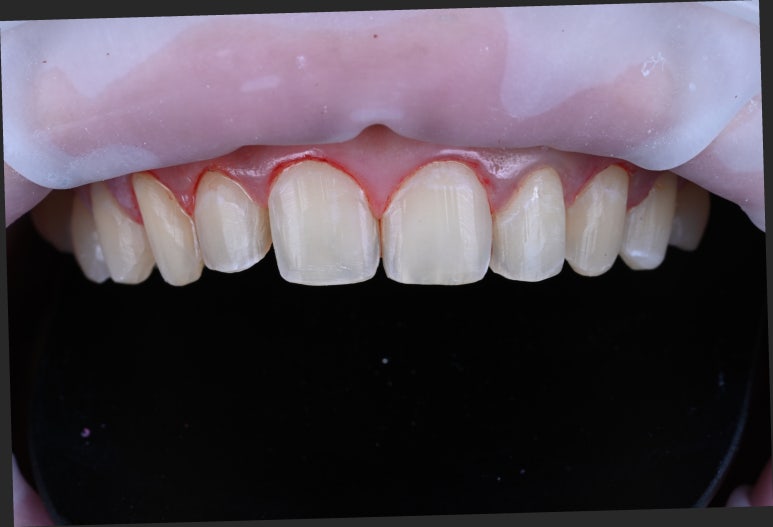

자연스러운 레브네이트 제작을 위한 잇몸성형을 하고나서,

치아를 다듬습니다. 0.3mm~0.5mm 정도.

잇몸 형태의 대칭을 맞추기 위해서, 전용 레이저를 이용해서 잇몸 성형을 시행합니다.

마취하고 하긴 하는데, 마취 풀려도 거~의 통증이 없습니다.

처음에 말씀드렸듯, 치아의 길이를 늘릴 수 있게끔 잇몸을 성형하여 아이보다는 성인의 치아에 가까운 비율로 수정하였습니다.

그리고 표면을 0.3~0.5mm 정도 다듬습니다. 아주 적은 양이기에 신중해야 하죠.

이것은 자세히 보면 오돌도돌한 치아 표면을 평평하게 다듬는 과정이고, 자연스럽게 라미네이트가 균일한 두께로 위치될 수 있게 하는데 필요한 과정입니다.

라미네이트를 붙이고 나면 어느 각도에서 보아도 균일한 색상으로 보이게 해야하기 때문에, 미세조정과정은 반드시 필요합니다 !!!!

잇몸 성형과 치아 삭제는 요만큼 정도 했었구요, 전 후 비교는 아래와 같습니다.